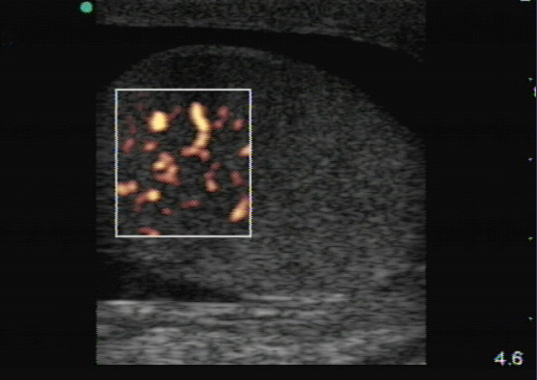

- On gray-scale ultrasound, orchitis is seen as an enlarged testicle with heterogeneous echogenicity. However, these findings are nonspecific and can be seen in many other conditions such as tumors, metastasis, infarct and torsion.

- Other sonographic findings include reactive hydrocele and scrotal skin thickening.

- Standard B-mode is not a reliable method to differentiate between orchitis and testicular torsion. For both orchitis and torsion, inflammation and edema can lead to enlargement and heterogeneous echogenicity of the testis. Color Doppler is helpful to differentiate between orchitis and torsion since blood flow in orchitis is increased in comparison with the unaffected side due to inflammation. 5-7 (Figure 6)

Figure 6. Orchitis. Marked increase in blood flow is seen along with a reactive hydrocele. (Courtesy of Michael Blaivas, MD)